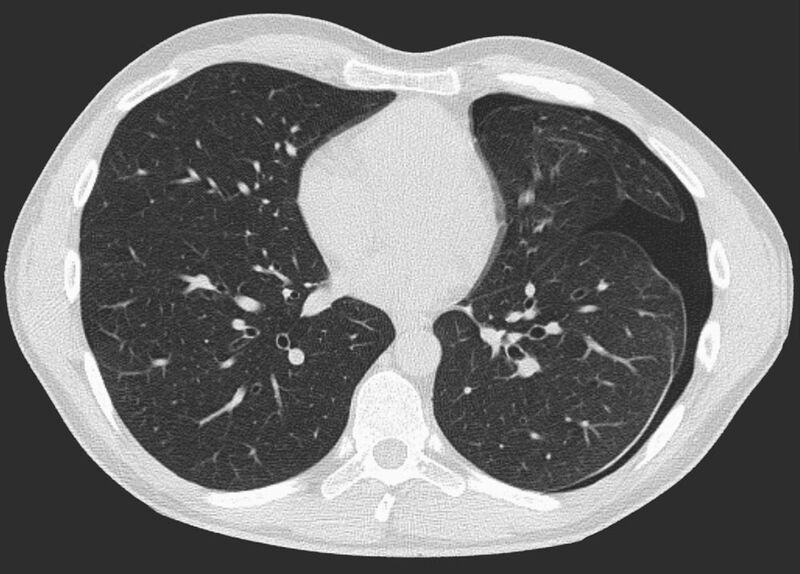

Thorax (Brustkorb)

• Entzündungen oder Tumore des Mediastinums und der Lunge

• Lungenembolie- Diagnostik

• hochauflösende Darstellung des Lungenparenchyms zur Abklärung chronischer interstitieller Erkrankungen wie z. B. Fibrosen, Emphysem, Bronchiektasen